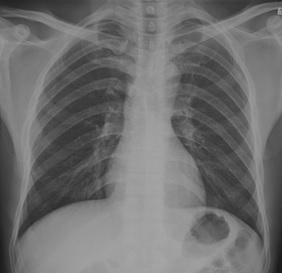

试题:根据下图请做出正确诊断

A.正常胸片

B.肺门淋巴结肿大

C.肺炎

D.主动脉型心(靴型心)